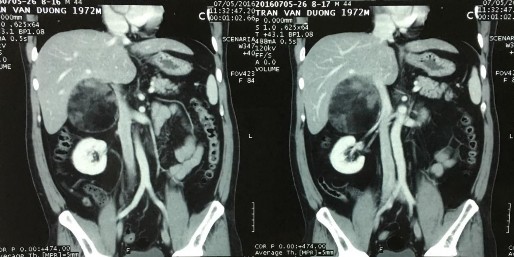

Phim CT scan bướu mỡ tủy thượng thận bên phải

[Trần Văn D., 44 tuổi, SNV: 2160063310]

Bệnh phẩm bướu mỡ tủy thượng thận bên phải